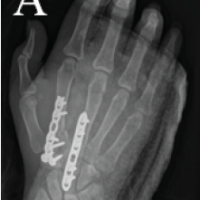

Ipsilateral fibular graft is harvested with its medullary canal reamed to stimulate medullary blood flow. It was contoured into triflanged shape and inserted into the fracture site of tibia. The distal tibial locking compression plate (LCP) was fixed back proximally with new screws. Post-operative period was uneventful. At 3 months follow-up, callus response was observed (Fig. 4). At subsequent follow-ups at 5 months and 9 months, it was observed that the fracture is progressing to union. At 10 months, the fracture united completely (Fig. 5) and the patient was walking without any support (Fig. 6).

Figure 4: Immediate post-operative X-ray after placing fibular strut graft.